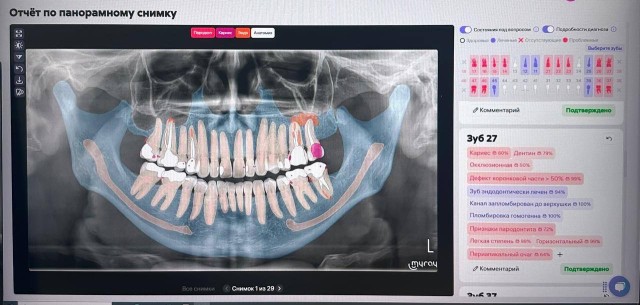

Как сообщает пресс-служба правительства региона, оренбургская областная стоматология внедрила систему анализа 2D- и 3D-рентгенографии на основе искусственного интеллекта в диагностику и лечение заболеваний зубов, костной ткани.

Согласно информации, в процессе анализа ИИ распознает мельчайшие отклонения, незаметные человеческому глазу. Затем программа создает детализированные отчеты о состоянии зубочелюстной системы, автоматически определяет каждый зуб и выявляет более 20 показателей на 2D-снимках и свыше 65 – на 3D – конусно-лучевой компьютерной томографии.

Такой метод позволяет выявлять патологии на ранних стадиях, обеспечивая своевременную и эффективную помощь.

При этом отмечается, что алгоритмы не заменяют диагностику врача. Они являются его инструментом повышения эффективности.